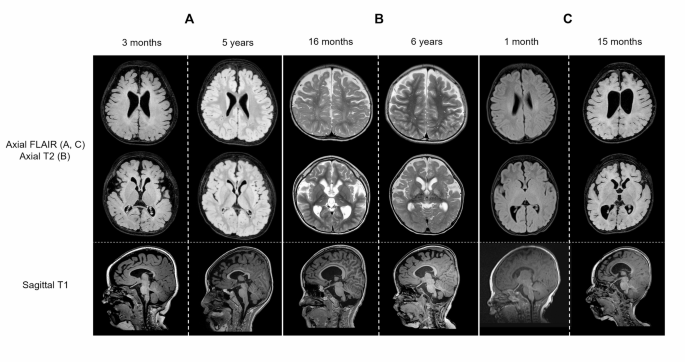

Brain MRI findings of Patients 1, 2, and 3. (A–C) Serial brain MRI images of Patients 1, 2, and 3. The first and second rows show axial FLAIR images for (A and C) and axial T2 images for (B). The last row shows sagittal T1 images. (A) MRI image of Patient 1 taken at 3 months (left) and 5 years (right). The axial images show prominent perivascular spaces and high signal intensity in the thalamus. The sagittal images reveal dysmorphic corpus callosum. (B) MRI image of Patient 2 taken at 16 months (left) and 6 years (right). The axial images show prominent perivascular spaces with T2 hyperintensity in the bilateral basal ganglia and the thalamus. (C) MRI image of Patient 3 taken at 1 month (left) and 15 months (right). MRI performed at 15 months shows diffuse cerebral atrophy with a thin corpus callosum.

Patient 1 was a 6-year-old male referred to the medical genetics clinic for intractable epilepsy. He was born with a birth weight of 3.46 kg without any perinatal problems. He initially showed normal growth and development. At 3 months of age, he began to show seizure-like movements, and MRI revealed cerebral atrophy (Fig. 2A). The initial EEG results were consistent with infantile spasms. Treatment with vigabatrin and prednisolone was successful at that time, but the seizures re-emerged at 8 months of age.

At 21 months of age, the patient exhibited generalized tonic–clonic seizures approximately once per week, despite treatment with topiramate, valproic acid, and lacosamide. Although the patient could control his head and babble, further developmental milestones were not achieved. Biochemical analysis revealed a borderline low plasma glutamine level, accompanied by an elevated ammonia level of 227 µg/dL. Sleep EEG showed diffuse delta activity in the background with a few centroparietal sharp waves. Seizure frequency decreased to once per month with the addition of perampanel at 4 years old. Follow-up MRI revealed symmetric T2 hyperintense lesions involving the thalamus, mammillary body, and brainstem with prominent perivascular spaces (Fig. 2A). At the last follow-up at 6 years of age, he was only able to sit with support, with no further developmental progress observed, suggesting developmental arrest.

Patient 2 was a 7-year-old male referred to the paediatric neurology clinic because of GDD. He was born at 38 weeks with a birth weight of 3.34 kg, without perinatal problems. His first seizure also occurred at 3 months of age, and by 16 months, he exhibited generalized tonic and myoclonic seizures approximately ten times per day. He was not able to control his head or speak any meaningful words. Brain MRI showed symmetric, ill-defined T2 high signal intensity in the bilateral basal ganglia, with prominent perivascular space at the white matter (Fig. 2B). Sleep EEG revealed diffuse high-amplitude polymorphic delta activity with posterior dominant spike-wave discharges. Plasma glutamine and ammonia levels were within the normal range.

Seizures persisted despite trials of multiple antiseizure medications and a ketogenic diet, but at 3 years of age, the seizures were controlled with the addition of valproic acid. The seizures recurred at 5 years of age after a febrile illness caused by pneumonia, with their frequency reaching up to 10 times per day at 6 years old. The seizures were initially stabilized after adding vigabatrin, but frequent relapses were observed despite the use of lamotrigine, levetiracetam, vigabatrin, and valproic acid. Although neurological examination revealed increased rigidity, the patient gained the ability to control his head and roll over. Nevertheless, no further developmental milestones were achieved even by 7 years of age. MRI showed cerebral atrophy with ventriculomegaly, along with T2 hyperintense lesions in the bilateral thalami and prominent perivascular spaces (Fig. 2B).

Patient 3 was a 4-year-old female who presented to the paediatric neurology clinic because of early-onset epilepsy. Generalized tonic seizures with facial flushing began at 4 weeks of age, which evolved into clonic seizures occurring approximately 10 times per day. MRI did not reveal any abnormalities in the brain (Fig. 2C). At 1 year of age, neurological examination revealed microcephaly and generalized spasticity with hyperreflexia. She was unable to control her head or make appropriate eye contact. Follow-up brain MRI revealed diffuse white matter volume loss with diffuse thinning of the corpus callosum (Fig. 2C), and interictal EEG showed diffuse rhythmic delta activity with frequent spike discharges in the left temporal region. The plasma and CSF glutamine levels were normal, although the ammonia level measured in an outpatient setting was elevated to 184 µg/dL.

The brain MRI findings consistently revealed prominent perivascular spaces and thinning of the corpus callosum in patients with AD type of the disease. Although hypomyelination or demyelination was also commonly observed in previously reported cases (7 out of 10 in AD cases), our patients did not have these features. Conversely, all our patients showed cerebral atrophy, and two of them (Patients 1 and 2) had T2 hyperintensity in the basal ganglia or the thalamus. Patient 3 did not have this feature, but the degree of cerebral atrophy and corpus callosum thinning were the most severe among our patients. In AR cases, abnormalities such as cerebral atrophy, attenuation of the gyri, and hypomyelination were found in Patients 14–16, whereas the MRI images of Patients 17–19 were structurally normal.